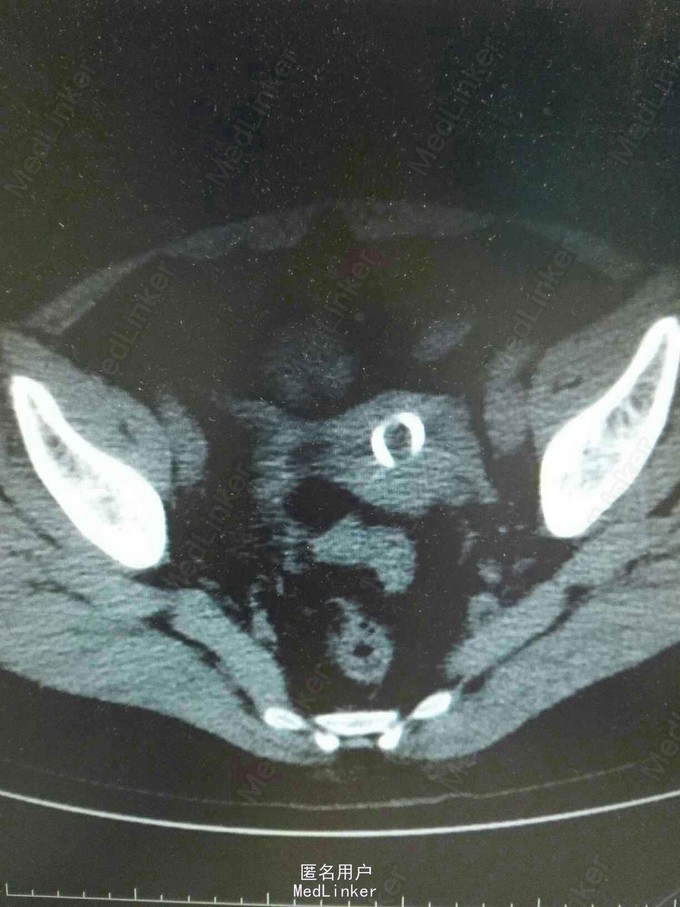

女,42岁,盆腔占位,根据所提供的ct图像,最可能的诊断是()

图7-1-5 女性盆腔ct影像(子宫底层面)

盆腔肿物,请大家帮忙看看!

查体 辅查 我院行盆腔ct示:节育器崁顿.

女性盆腔定位 ct 像